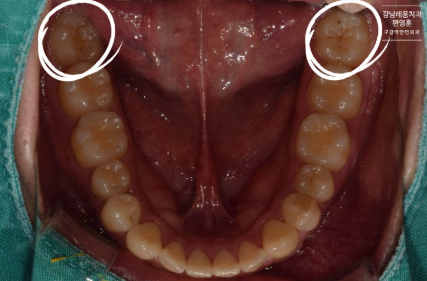

사랑니 통증 방치 사례

다음은 실제 사랑니 통증을 방치하다

뒤늦게 발치를 진행한 사례입니다.

#CASE

사랑니 통증 방치 후

잇몸뼈 소실

해당 환자분은 사랑니쪽의

지속적인 통증을 느껴오셨으나

일이 바빠 약을 먹으며 버티시다

극심한 통증으로

뒤늦게 발치를 진행한 케이스입니다.

상태를 확인해보자

방치된 사랑니 주변 염증으로

옆 어금니의 잇몸뼈가 소실되어

뿌리가 지탱하지 못해 흔들리는 상태였습니다.